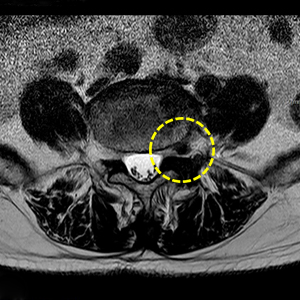

좁아진 척추관과 탈출된 디스크

마이크로 척추수술 후 넓어진 척추관

탈출된 디스크

마이크로 척추수술 후 제거된 탈출디스크

1.5cm~3cm 정도 피부 절개 후 미세 현미경을 이용해 수술 부위를 확대해 신경을 누르는 뼈를 일부분 제거하고 탈출된 디스크, 인대를 제거하여 신경이 눌리지 않게 해주는 수술입니다.